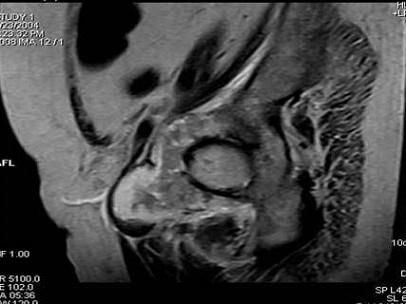

问题 患者 男,38岁,感觉左髋部疼痛,并逐渐加重,体检:左髋部明显肿胀压痛,无明显发热,请选择最佳诊断 ( )

选项 A、软骨肉瘤 B、软骨黏液纤维瘤 C、纤维肉瘤 D、骨肉瘤 E、骨巨细胞瘤

答案 A